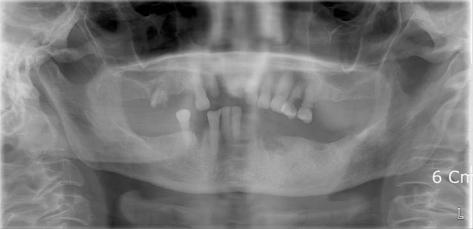

The advent and wide use of antibiotics have decreased the incidence of deep neck infection. When a deep neck infection does occur, however, it can be the cause of significant morbidity and death, resulting in airway obstruction, mediastinitis, pericarditis, epidural abscesses, and major vessel erosion. In our clinic, a patient with diffuse chronic osteomyelitis of mandible and fascial space abscess and necrotic fasciitis due to odontogenic infection at the time of first visit came. We successfully treated the patient by early diagnosis using contrast-enhanced CT and follow up dressing through the appropriate use of radiographic images.